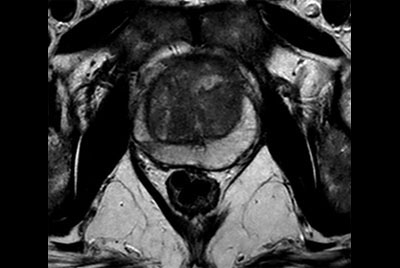

Prostate with dual coil set-up